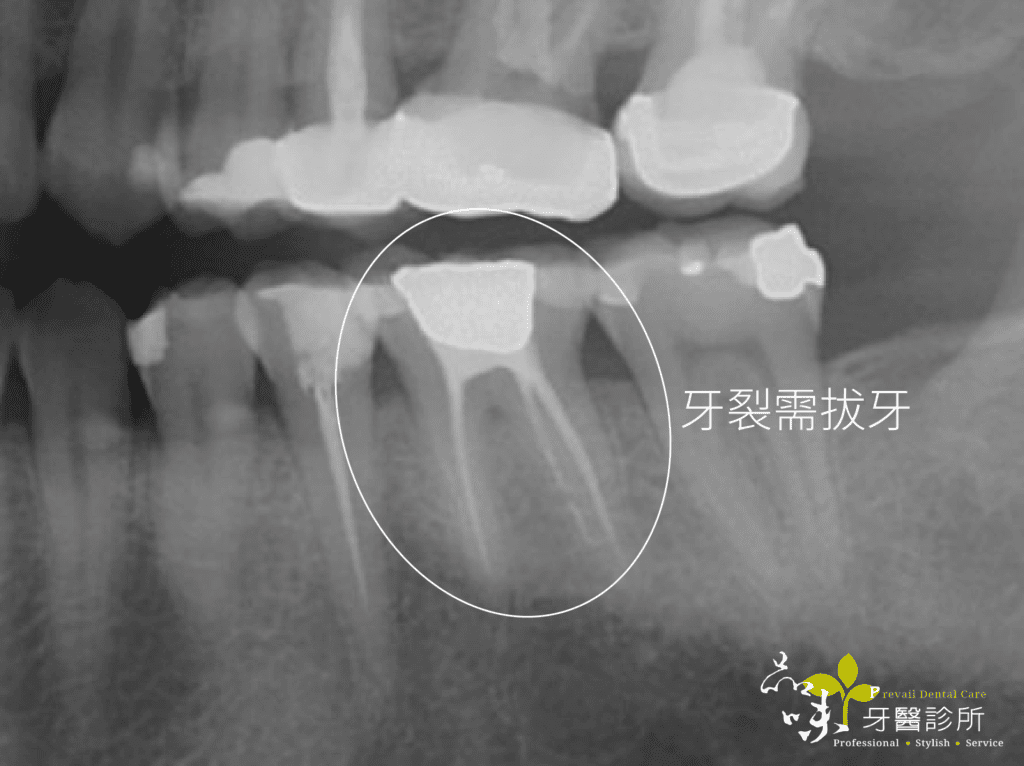

下午診間走進一位牙齒劇烈疼痛的陳先生(化名)。左手捧著下巴,疼痛難耐地說:「醫師,今天不小心咬到骨頭,現在只要一喝水就感到抽痛,痛到無法咬東西,請問這顆牙怎麼辦?」

經過臨床檢查後,我發現這顆牙已呈現牙根斷裂的狀況,依目前醫療常規只能把斷裂的牙齒拔除。

「剛剛我分析了你的 X 光與 CT 電腦斷層,你這顆牙齒或許可以做即拔即植的治療喔,幫忙你比較快有牙齒可以用!」

文首提到牙裂的陳先生,當天下午就安排了手術。在一系列數位資料蒐集後,進行藍光導航植牙。傍晚陳先生的牙齒就不疼了。